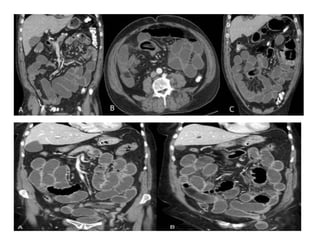

El estudio de Tomografía por

Computadora tiene una sensibilidad

del 80 al 90%

HALLAZGOS:

 Dilatación proximal de intestino

 Descompresión distal de intestino

 Contraste intraluminal que no pasa

más allá de la obstrucción

 Intestino distal con poco gas

• La presencia de asa intestinal en

forma de U o de C indica obstrucción

de asa cerrada

• Neumatosis intestinal, gas en la

vena porta, opacidad mesentérica y

captación deficiente del contraste

intravenoso en la pared hace pensar

en estrangulamiento

El estudio deTomografía por Computadora tiene una sensibilidad del 80 al 90% HALLAZGOS:  Dilatación proximal de intestino  Descompresión distal de intestino  Contraste intraluminal que no pasa más allá de la obstrucción  Intestino distal con poco gas

• La presenciade asa intestinal en forma de U o de C indica obstrucción de asa cerrada • Neumatosis intestinal, gas en la vena porta, opacidad mesentérica y captación deficiente del contraste intravenoso en la pared hace pensar en estrangulamiento